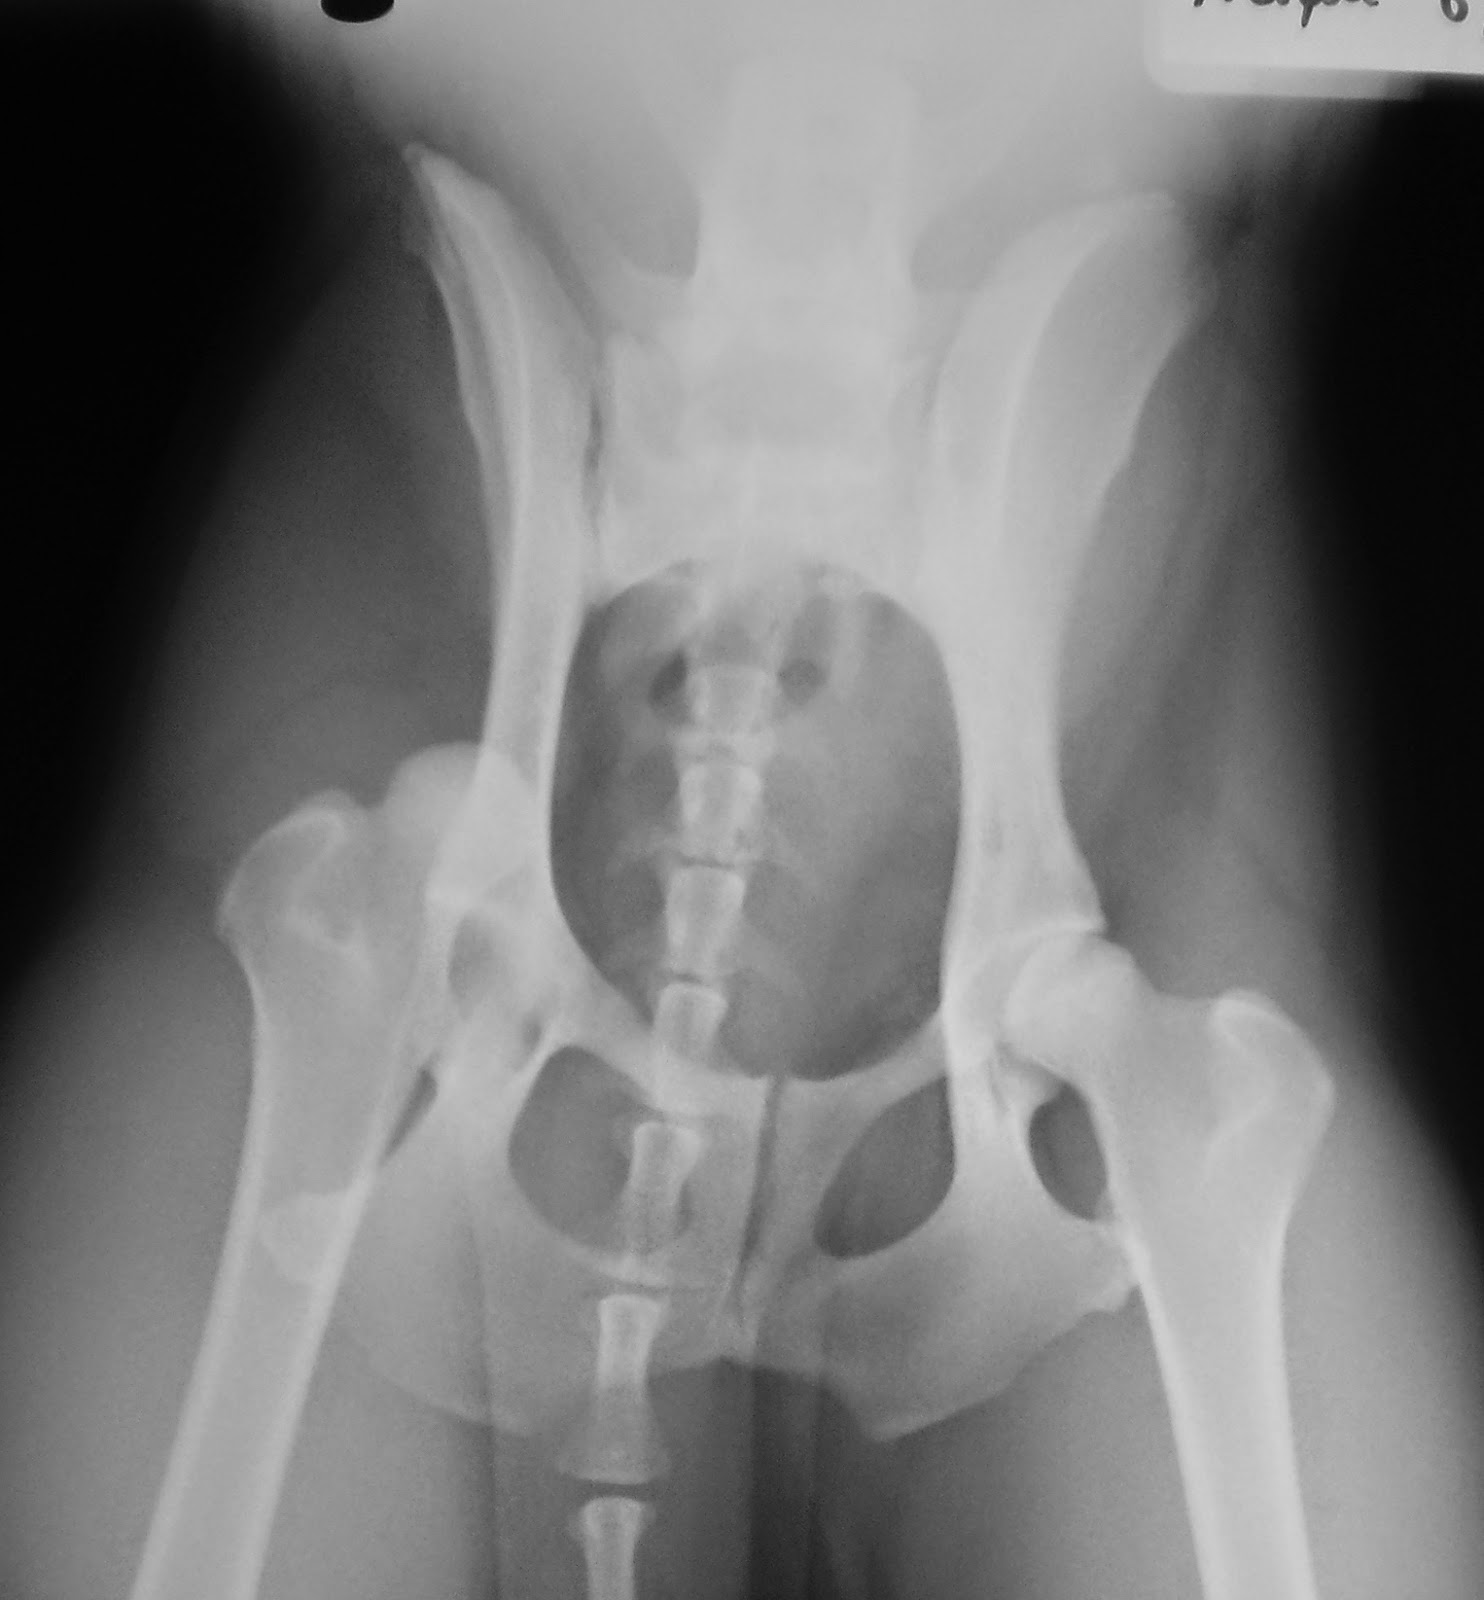

Για την επιβεβαίωση της διάγνωσης του εξαρθρήματος του ισχίου, η πύελος ακτινογραφήθηκε σε ύπτια θέση (Εικ. 2) με το σκύλο υπό γενική αναισθησία.

Εικ. 2: Ύπτια ακτινογραφία πυέλου: εξάρθρημα δεξιού ισχίου.